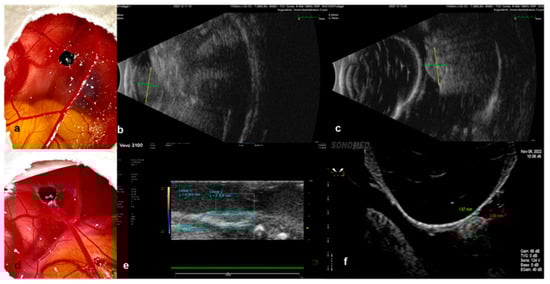

3.2.2. Infrared Imaging, Optical Coherence Tomography and Angiography, and Fluorescein Angiography

2.4.2. Optical Coherence Tomography and Infrared Imaging

2.4.3. Optical Coherence Tomography Angiography

2.4.4. Fundus Fluorescein Angiography